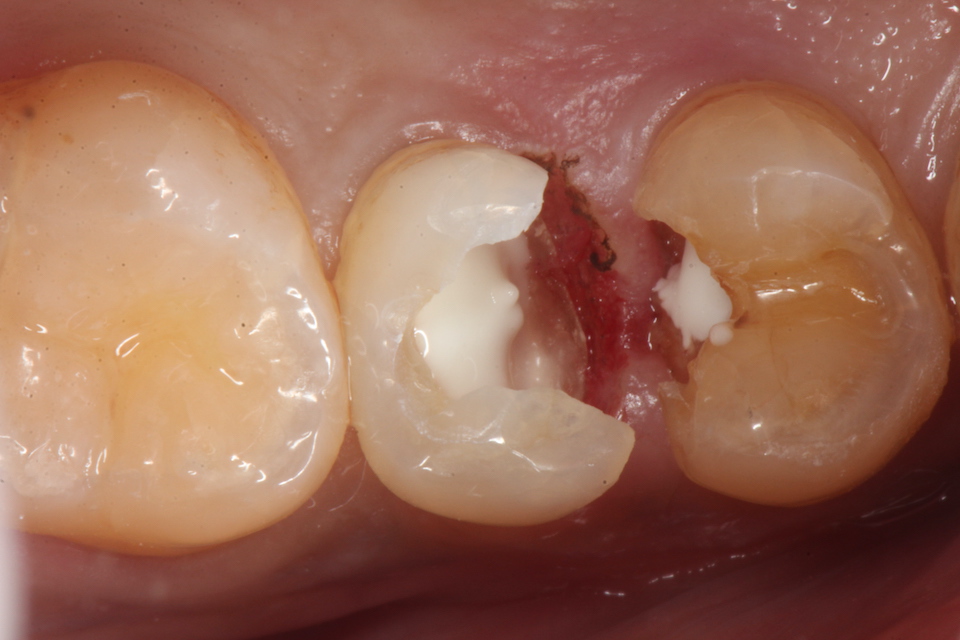

下顎7番の頬側歯茎部カリエスの原因 2025.06.04